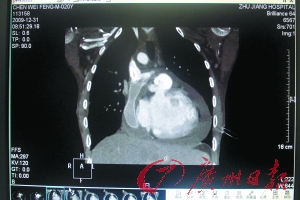

广州日报:“半心人”成功修心

作者:翁淑贤阿辉心脏只有“一房一厅”。生来只有“一心房一心室”奇迹般活到20岁本报讯(记者翁淑贤通讯员吴源周、胡琼珍、孙健摄影报道

小伙天生“半颗心” 修心成功“黑人”变红润

正常人心脏有左、右心房和左、右心室各一个,被喻为“两房两厅”,而20岁的阿辉(化名)心脏却只有“一房一厅”。这种先天的心脏缺陷使得